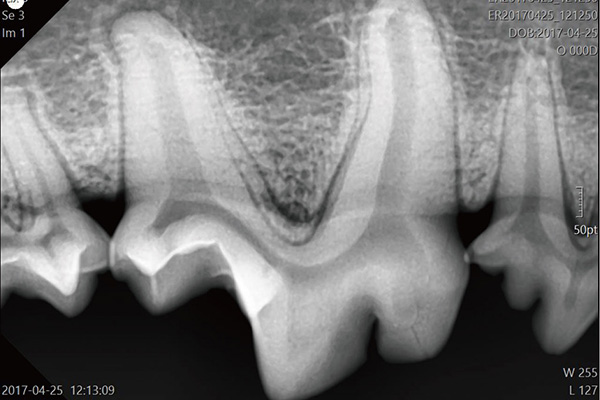

小動物専用X線撮影システム

ポジショニングのしやすさ、X 線条件の設定のしやすさ、被ばくの低減、そして高画質など優れた性能を実現し、獣医療の現場をしっかりとサポートします。

画像処理ユニット

画像処理と多彩な機能で、正確・迅速な診断をサポート。

動物専用医療用X線装置

従来よりも少ないX線量で照射できるため、動物とスタッフへの負担を軽減しながら撮影を行うことが可能です。

動物用デジタルX線センサー

最先端CMOSセンサーを採用し細部まで鮮明に表現します。撮影後3-5秒程度で撮影した画像が表示できるため、麻酔時間の短縮になります。